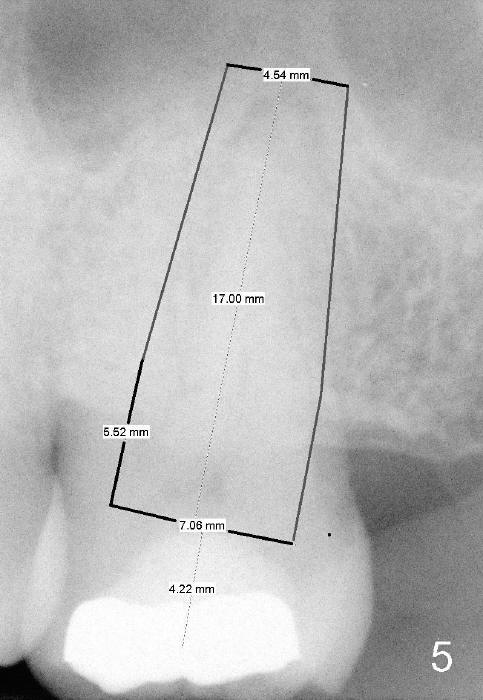

A 52-year-old black man fails to return to finish root canal therapy for the tooth #15; ultimately it is non-salvageable (Fig.1-3). The tooth has 3 basically fused roots (Fig.4 black (buccal) and red (palatal) outlines), above which is the sinus septum (*). By inserting an immediate implant into the sinus septum, primary stability should be high (Fig.5 vs. 6).